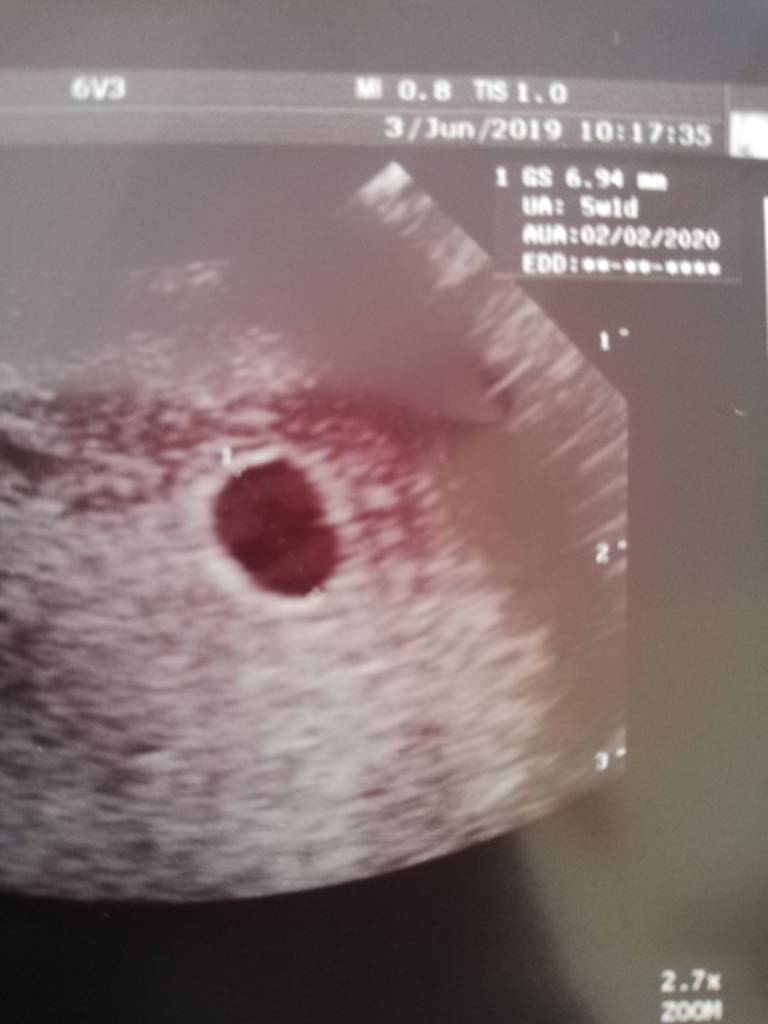

Lutowe 2020

Super <3 gratuluje! Nie mogę się doczekać ąż zobaczę moją fasolkę ;) jednak to jest duże przeżycie ;)

Może powinnam jeszcze raz zbadać sobie poziom beta hcg i progesteron? Serio mam myśli że może tam nic nie ma :/ a do lekarza na usg mam dopiero na 26 czerwca